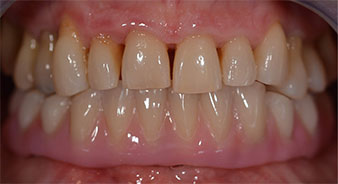

Una volta trascorso il tempo necessario per la osteointegrazione, è stato possibile prendere l'impronta definitiva degli impianti e, poi, è stata realizzata la protesi definitiva (Fig. 19 e 20). A questo punto, il dentista e la paziente hanno potuto decidere insieme se utilizzare delle faccette in ceramica o in vernice acrilica, con una struttura in zirconio o metallo. In questo caso, il Dott. Pascu e il suo team hanno preferito delle faccette in vernice acrilica, a seguito della prognosi difficile sulla dentatura mascellare e sulla posizione allungata del dente 24. Questo tipo di faccette è solitamente molto più facile da adattare e, di conseguenza, può essere modificato per rispondere alla nuova situazione della mascella.

osteointegrazione

Fig. 19

impianti

Fig. 20